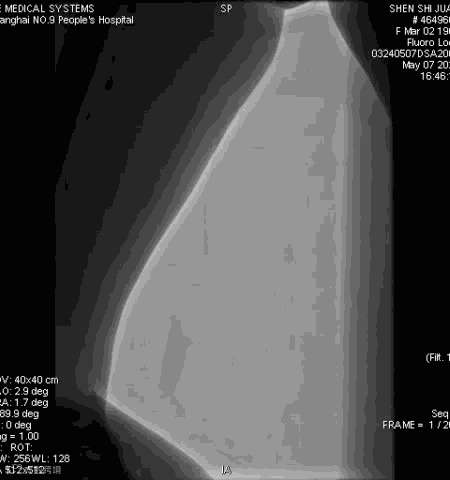

手术过程

抽吸结果